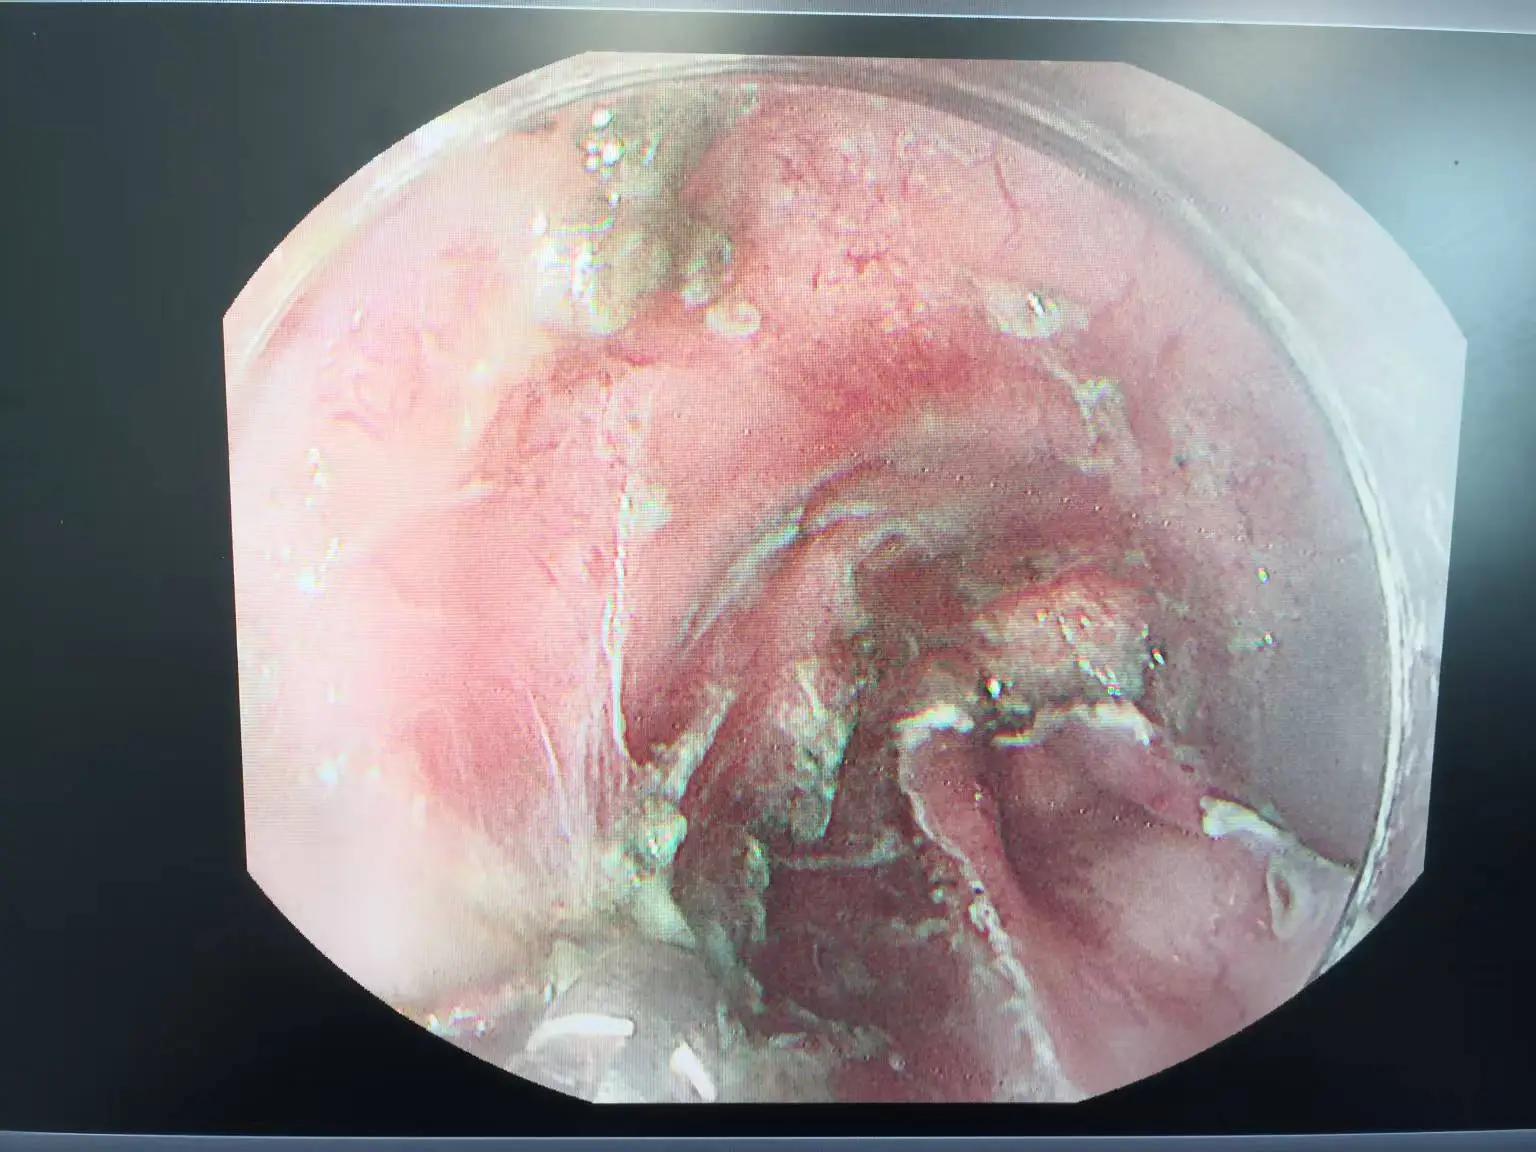

术前胃镜(距门齿约40cm处病灶)

据了解,一名患者因上腹部不适,外院胃镜检查提示食管距门40cm处黏膜粗糙,活检病理提示重度异型增生,遂来医院就诊,完善检查胃镜检查提示食管距门齿约40cm近全周病变,FICE电子染色呈茶褐色改变,考虑食管早癌,CT未见明显转移,病理示高级别上皮内瘤变,符合食管早癌ESD治疗的适应证。